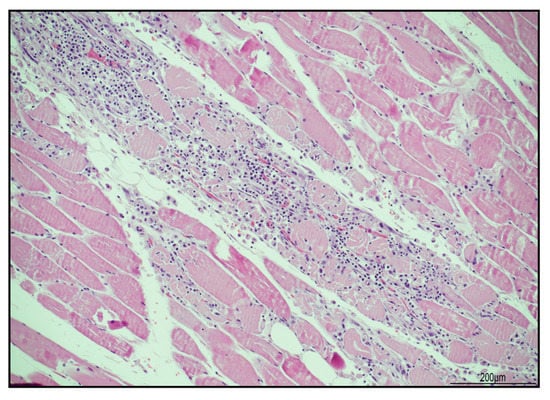

2.3. Histological Findings